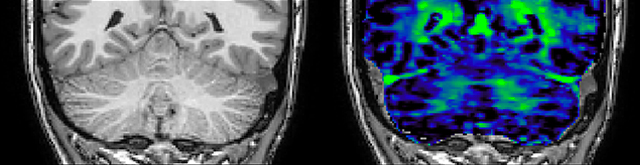

The techniques for measuring myelin have changed a lot over the years. “Since we are using the Elition, our myelin water images are much better. We're now acquiring 1 x 2 x 5 mm voxels and displaying at 1 x 1 x 2.5 mm. For a whole brain we can now measure the fraction of water in the myelin component in only about five or six minutes,” Dr. MacKay says.

of limiting MWI to the brain, even without the cerebellum, we can now spend about the same amount of time and scan the whole brain and the cervical spinal cord, which is a huge boost for us.” Dr. Rauscher says, “For MWI we perform 3D T2 with 32 or more echoes. This used to take a long time, but with Compressed SENSE we can decrease this to ten minutes for the whole head. Because of the large field of view (FOV) on the readout direction, we even get information from the brainstem, which we previously missed when we were using the GRASE approach. Having the whole head scan is nice because it has spatial resolution, orientation and FOV that are comparable to the standard 3D clinical MS scans, including the FLAIR and 3D T2, and a 3D T1 for brain volume.”

Spinal cord coverage

Smaller, more isotropic voxels

Excellent detail in quantitative maps

Images courtesy of Adam Dvorak, Department of Physics and Astronomy, University of British Columbia

According to Dr. MacKay, MWI images benefit from Elition’s high quality gradients. “We need good gradients because we want to be able to do multi-echo sequences that have short TE times.”

Dr. Rauscher says, “With better gradients we can use a shorter echo spacing on the spin echo, so we get better sampling of the rapidly decaying myelin signal, which typically has T2 of around 10-20 milliseconds at 3 Tesla. If we can reduce echo spacing from about 8 to 5-6 milliseconds, we get a much better sampling of the short decay component and increase our SNR, which is a big advantage. The same is true for multi-echo gradient echo which we use for susceptibility mapping and for mapping venous vessels in MS.”